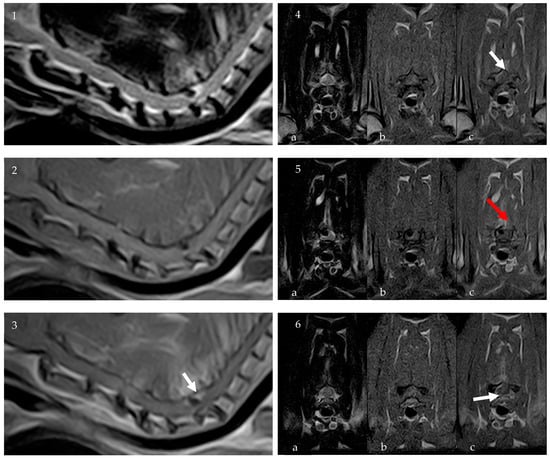

2. Case Description